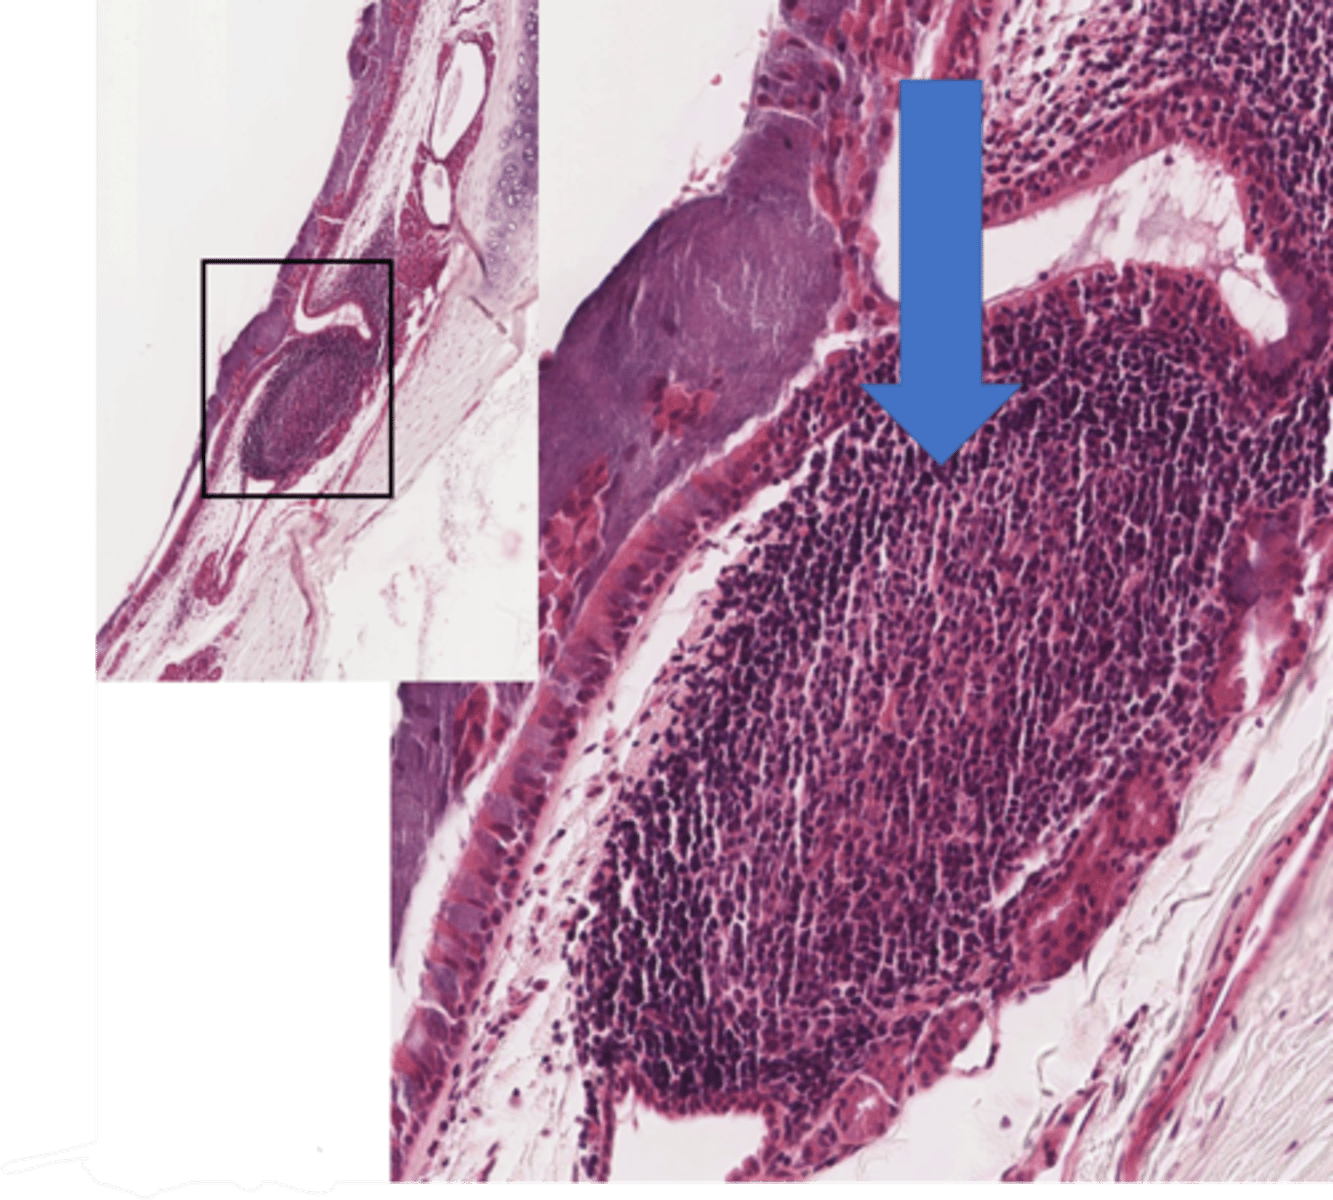

Identify the type of airway

bronchi

Identify this type of airway

bronchioles

T/F: Only bronchi have cartilage

true

Identify the type of bronchiole

terminal bronchioles

respiratory bronchioles

Identify the airway segment between the lines.

alveolar ducts

Identify the starred portion of the airway

alveolar sacs

Identify these unattached cells in this alveolus

pulmonary alveolar macrophages

Name the barrier located here

blood air barrier

What cells make up the blood air barrier

type 1 pneumocyte and endothelial cells